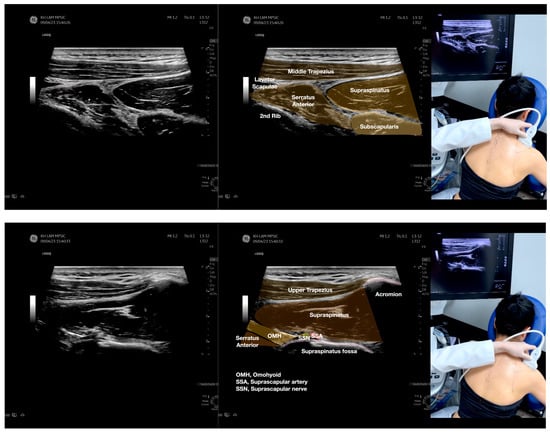

Figure 3.

Sonoanatomy of the lateral boarder of the scapular, its related muscles, and the infraspinatus fascia. Video S7 has demonstrated the step-by-step scanning techniques of these structures shown in this figure. Available online: https://www.dropbox.com/s/891m19vvw6bak34/Figure%203.docx?dl=0 (accessed on 1 January 2023).